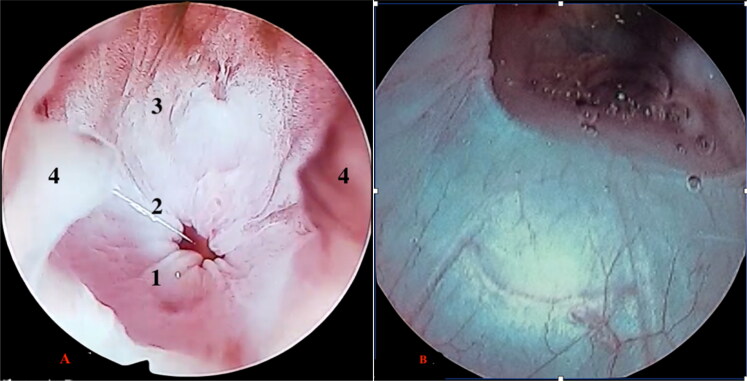

这篇文章首次尝试介绍了在积水马尾鱼(Varananus cumingi)和大马尾鱼(Varananus macraei)泄殖腔区域使用内窥镜技术的实用性和可行性。这种方法既可用于诊断,也可用于治疗,还可通过观察尿道(雄性尿道末端为盲端,雌性尿道末端由两个代表输卵管出口的孔组成),为性别鉴定提供早期方法。在这种情况下,通常采用的性别鉴定技术,如后腔距检测,已显示出不可靠的一面。这项研究对来自一家私人繁殖场的十只约一岁大的标本进行了检查,在此之前还对它们进行了全面的临床评估,以确认它们的总体健康状况。所有受试者都接受了镇静剂治疗,从而可以对解剖结构、泄殖腔健康状况和性别进行评估。这项研究及其发现可为解决这些物种数量下降的问题提供重要依据,尤其是已被世界自然保护联盟列为 "濒危 "物种的大鳞蛙。

This article attempts to present, for the first time, the usefulness and feasibility of using endoscopic techniques in the cloacal region of Varanus cumingi and Varanus macraei. This method can serve both diagnostic and therapeutic purposes, as well as offering an early approach to sex determination through the observation of the urodeum which in males ends in a blind end while in females it consists of two ostia which represent the outlets of the oviducts. In this context, commonly employed sex determination techniques, such as post-cloacal spur detection, have shown unreliability. The study involved the examination of ten specimens, approximately one year old, from a private breeding farm, following a complete clinical evaluation to confirm their general state of health. All subjects underwent sedation, which allowed the evaluation of anatomical structures, the health status of the cloaca and the determination of sex. This study and its findings may provide a critical basis for addressing population declines of these species, particularly for V. macraei, which has already been classified as 'endangered' by the IUCN.